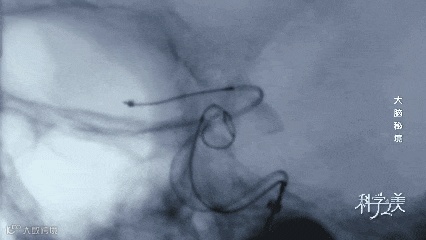

这是专门针对血管成像的数字减影影像,不同于普通X光片的平面影像,数字减影血管造影技术,可以将细到数微米的脑血管单独分离出来,它就像大脑血管网络的卫星导航,帮助医生更加明确血管病变的通路。

这是一种大脑中常见的脑血管疾病,叫“颅内动脉瘤”,就像脑血管上鼓起的大泡泡。

此刻,奔腾的血液汹涌地流进泡泡的内部,每一次冲击,都有可能使得原本就薄如蝉翼的血管壁突然爆破。

如今,微创的弹簧圈栓塞术成为治疗颅内动脉瘤的主流方式。

这些肩负使命的“迷你小战士”从大腿根部的股动脉开始,穿越大半个身体,最终到达大脑深处。

这是一个极其优雅的释放过程。在手术过程中,医生可以对释放出的弹簧圈进行收放自如的控制,如果释放效果不满意,可以重新再放,这样就大大提高了手术的安全度。

直到一切满意后,医生才会将弹簧圈与导丝分离,让它永远留在动脉瘤里。

此时,“致命泡泡”的内部,盘根错节的弹簧圈让血液逐渐变成凝固的血栓,成为阻挡后来者的坚固堡垒。这颗“不定时炸弹”被从内部攻陷。